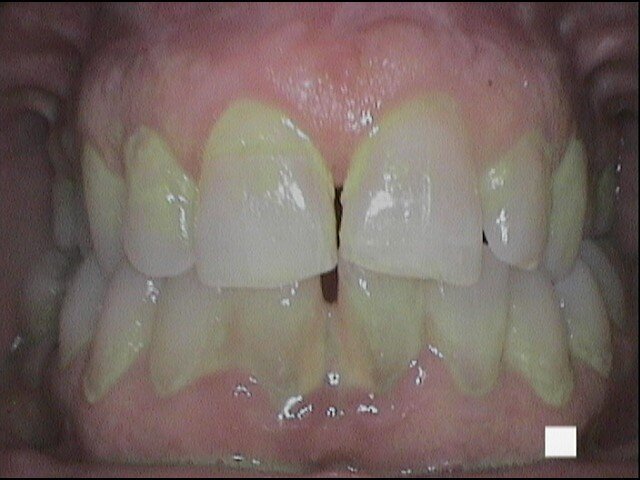

Passiamo poi al debridment parodontale con ablatore pizoelettrico Comby Touch Mectron e successivamente facciamo visualizzare al paziente le grosse concrezioni di tartaro presenti nell’area linguale e facciamo osservare la considerevole ampiezza biologica dello spazio interprossimale dato dalla recessione della papilla interdentale (Figg. 5a-5c). Mostriamo quindi la necessità di utilizzare lo scovolino professionale GUM TRAV-LER (Fig. 5d) con ampiezze diverse per essere efficaci nel controllo del biofilm batterico a livello interincisivo. Al follow-up il paziente presenta indici clinici sensibilmente migliorati e riferisce di sentirsi soddisfatto perché dotato finalmente di strumenti in grado di agevolarlo nel difficile compito di tenere sotto controllo l’efficacia della sua igiene orale domiciliare (Figg. 6a-6c).